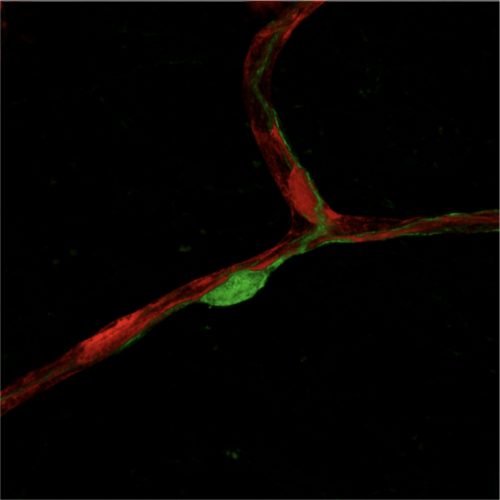

Endothelial cell–pericyte crosstalk governs organ homeostasis

The crosstalk between endothelial cells and pericytes is essential for angiogenesis, vessel remodeling, and the maintenance of vascular homeostasis. Dysregulation of endothelial cell–pericyte interactions impairs angiogenesis and vascular integrity, which are hallmark features of various diseases, including cancer, diabetic retinopathy, liver fibrosis, lung edema, autoimmune diseases, and neurodegenerative disorders. Our research focus on systematically mapping the endothelial cell–pericyte interaction landscape in both normal and pathological conditions. By unraveling these mechanisms, we aim to develop targeted therapies that restore the disrupted endothelial cell-pericyte interactions driving these diseases, offering innovative treatment strategies where conventional approaches fall short.